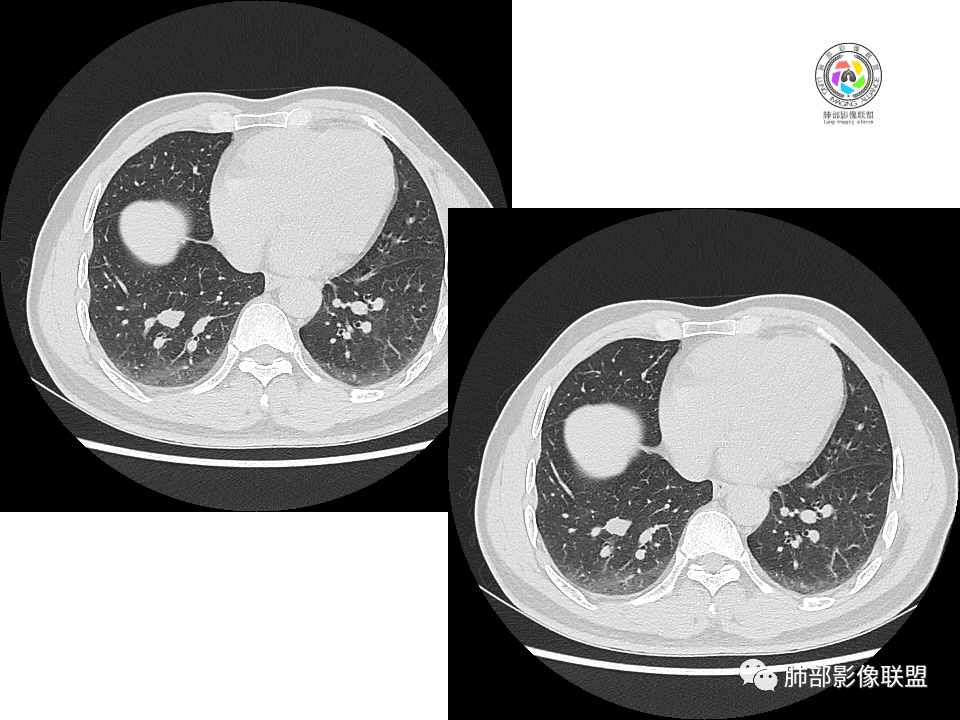

右肺下叶背段胸膜下见团块影,边缘清,其后基底段见一扁平状结节,各见‘’平直及桃尖"征,均轻度强化,右肺上叶背段及中叶外侧段分别少许纤维化灶及部分卫星病灶,一元考虑TB,与隐球菌鉴别!

右肺下叶胸膜下类圆形团块,边缘光滑无毛刺分叶,强化均匀无坏死,另血管旁小结节平直桃尖,上叶小斑片影,考虑结核或者真菌感染。

右肺下叶背段胸膜下见一边缘稍模糊、浅分叶结节灶,密度均匀,似乎轻度均匀强化(具体CT值看不出来),与胸膜锐角相贴,似有平直征和桃尖征。此病灶前内侧还有类似小结节,轻度强化,右肺上叶后段有斑片状稍高密度影:考虑良性病变,炎性结节可能。

晨读,右肺下叶背段胸膜下见肿块影,边缘清晰,未见与气管相连通,右下叶见结节影边缘清晰,两处病变密度均匀,同步不明显强化,中叶外侧段斑点状影,树芽征,考虑1良性病变,结核?隐球菌?2淋巴瘤待除外。

右肺下叶背段胸膜下宽基底团块状占位,浅分叶,边界清晰,胸膜下脂肪间隙清晰,背段支气管管壁似乎增厚,未见明显强化。外侧基底段血管束间结节,边界清晰,亦未见明显强化。中叶外侧段见少许树芽征象。纵隔未见明显肿大淋巴结。我先猜个结核。

男性,49岁,体检发现,右肺下叶背段胸膜下见肿块,边界清楚,边缘光滑,胸膜下脂肪间隙存在,有分叶,无毛刺,均匀强化,内无坏死,右肺下叶血管束间不规则实性结节,边界清楚,无明显强化,中叶少许斑片状高密度影,纵隔未见明显增大淋巴结,考虑良性病变。

2.右肺下叶背段胸膜下块影,边界清楚光整,上下极见磨玻璃晕,未见明显分叶毛刺和棘状突起,未见胸膜凹陷或胸壁侵入。密度均匀,轻度不均匀强化。未见支气管进入。

3.右肺中叶外侧段胸膜下散在小片影,磨玻璃密度为主,边界不清,支气管相关。符合炎性特征!

4.右肺下叶基底段支气管血管束旁小结节影,边界清楚,强化不明显。注意,这结节在“遥远的”基底段。